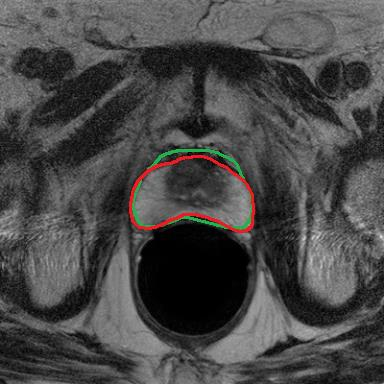

Modern deep neural networks struggle to transfer knowledge and generalize across diverse domains when deployed to real-world applications. Currently, domain generalization (DG) is introduced to learn a universal representation from multiple domains to improve the network generalization ability on unseen domains. However, previous DG methods only focus on the data-level consistency scheme without considering the synergistic regularization among different consistency schemes. In this paper, we present a novel Hierarchical Consistency framework for Domain Generalization (HCDG) by integrating Extrinsic Consistency and Intrinsic Consistency synergistically. Particularly, for the Extrinsic Consistency, we leverage the knowledge across multiple source domains to enforce data-level consistency. To better enhance such consistency, we design a novel Amplitude Gaussian-mixing strategy into Fourier-based data augmentation called DomainUp. For the Intrinsic Consistency, we perform task-level consistency for the same instance under the dual-task scenario. We evaluate the proposed HCDG framework on two medical image segmentation tasks, i.e., optic cup/disc segmentation on fundus images and prostate MRI segmentation. Extensive experimental results manifest the effectiveness and versatility of our HCDG framework.